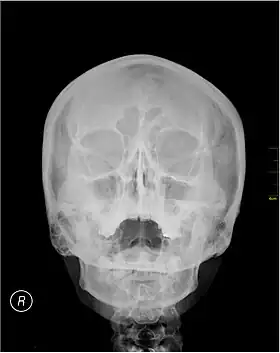

| Waters' view | |

Waters' view (also known as the occipitomental view) is a radiographic view of the skull. It is commonly used to get a better view of the maxillary sinuses. An x-ray beam is angled at 45° to the orbitomeatal line. The rays pass from behind the head and are perpendicular to the radiographic plate. Another variation of the waters places the orbitomeatal line at a 37° angle to the image receptor. It is named after the American radiologist Charles Alexander Waters.

Waters' view can be used to best visualise a number of structures in the skull.

- Maxillary sinuses.

- Frontal sinuses, seen with an oblique view.

- Ethmoidal cells.

- Sphenoid sinus, seen through the open mouth.

- Odontoid process, where if it is just below the mentum, it confirms adequate extension of the head.

The frontal sinus may not show the frontal sinus in detail.[1]

Typically, the x-ray beam is angled at 45° to the orbitomeatal line.[3] Another variation of the waters places the orbitomeatal line at a 37° angle to the image receptor,[4] or 30°.[5]